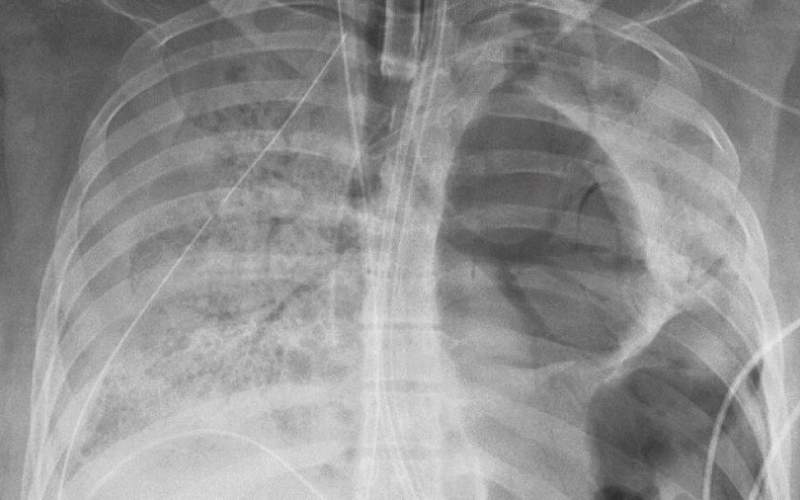

وأشار المستشفى إلى أن المريضة هي شابة من أصول أميركية لاتينية كانت في صحة جيدة، غير أنها تعرضت لإصابة خطرة بفيروس كورونا المستجد لدرجة أنها أدخلت لستة أسابيع إلى العناية الفائقة حيث أبقيت على جهاز التنفس الاصطناعي وربطت بآلة خاصة تقوم مقام القلب والرئتين تلقائيا.

وقالت الاختصاصية في الطب الرئوي في "نورث ويسترن"، بيت مالسين، إن هذه المريضة "بقيت على مدى أيام صاحبة الإصابة الأخطر في قسم الإنعاش لمرضى كوفيد-19 وفي المستشفى برمته على الأرجح". لكن تعين الانتظار لإنجاز عملية الزرع قبل أن تصبح نتيجتها سلبية في فحص كورونا.